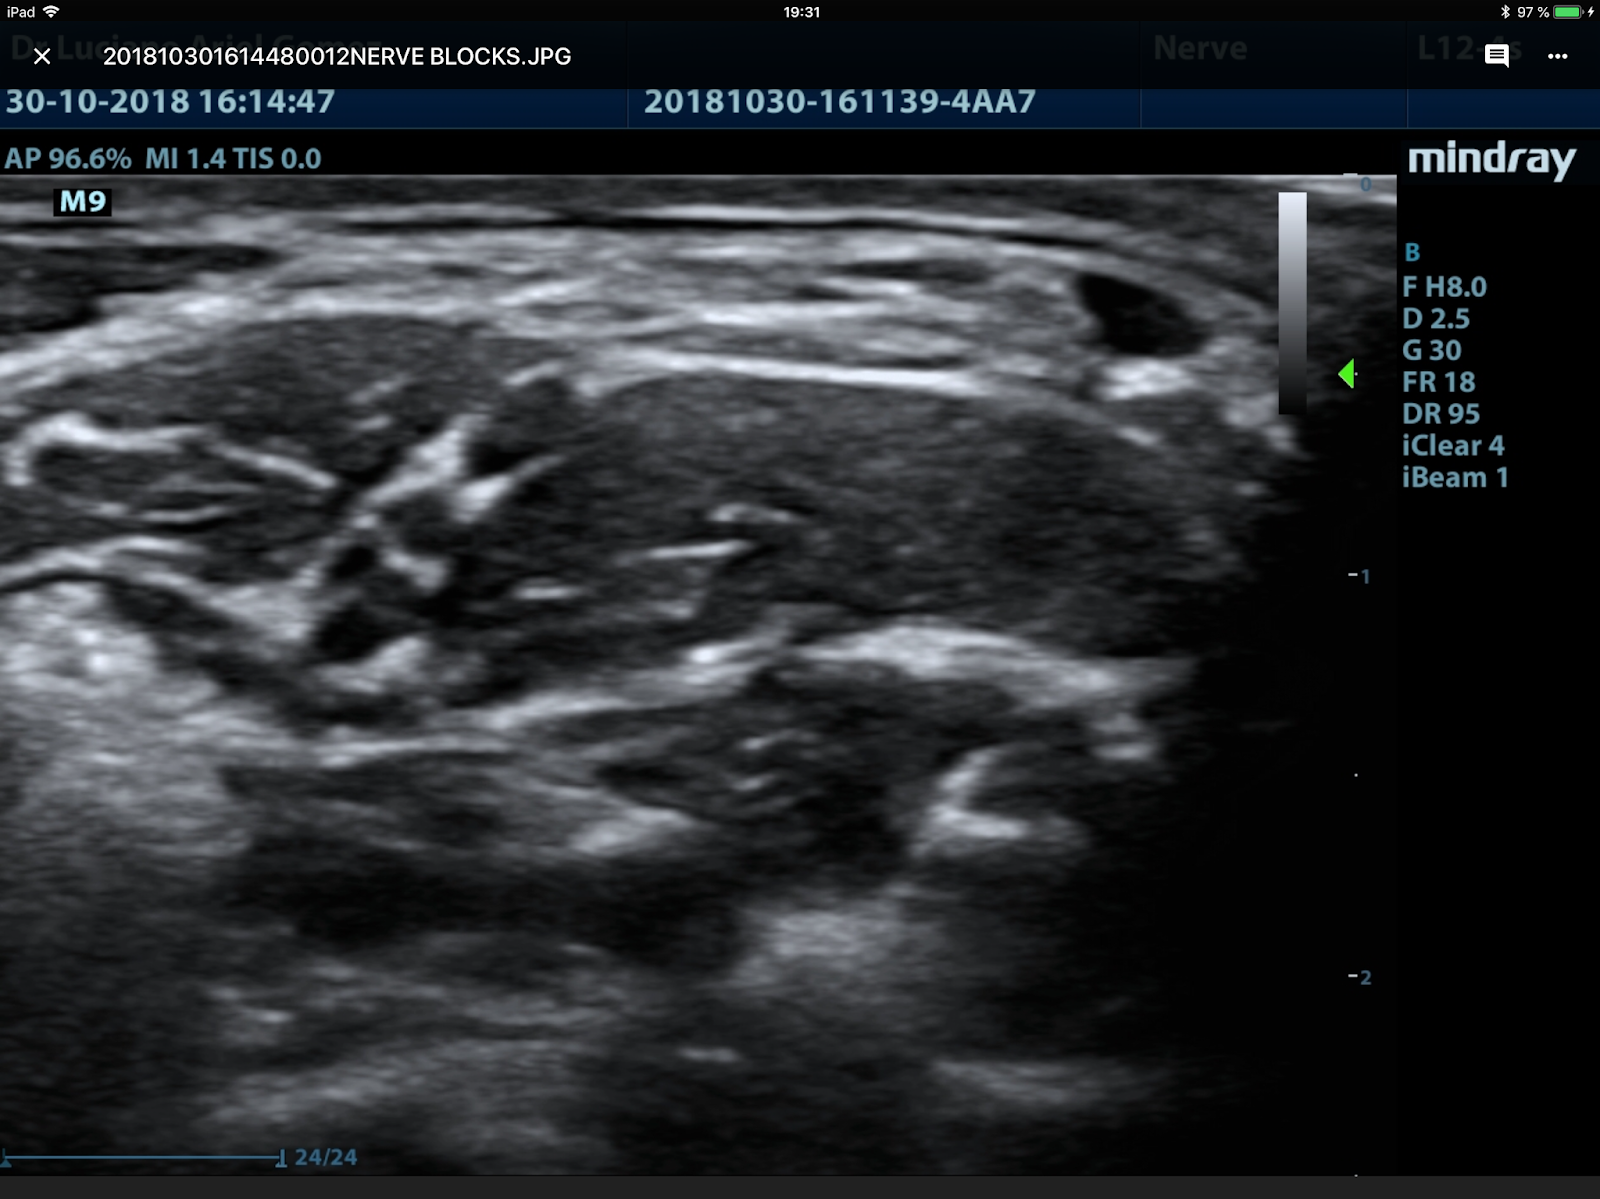

2-Del interescalénico y el bloqueo frénico. La próxima imagen ecográfica de la zona del plexo a nivel C6, medial está a la izquierda y lateral a la derecha. Estaría tomada un poco por debajo del cricoides.

Explicado EA escaleno anterior EM escaleno medio. Los redondeles negros son los troncos del plexo. Esta imagen se llama “en semaforo” y corresponde a un plexo alto más o menos a la altura del cricoides.